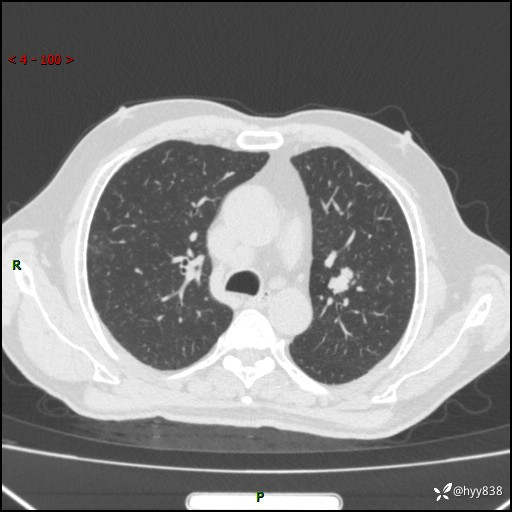

胸部CT平扫